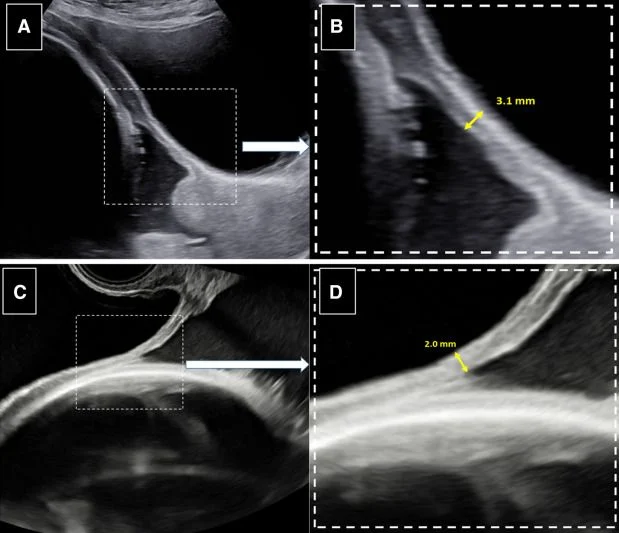

(A) Transabdominal examination of the lower segment by ultrasound. (B) The portion of the image where the lower segment appears thinnest is zoomed in and the thickness is measured. (C) The examination is repeated by transvaginal ultrasound in the same patient. (D) While the measurement was 3.1 mm by abdominal ultrasound, the thinnest measurement of 2.0 mm is retained.”